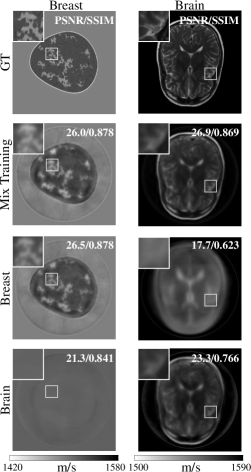

Refer to caption

Figure 6: USCT FWI reconstruction using NBSO trained on different datasets. In descending order, the rows correspond to the ground-truth alongside FWI results from NBSO trained on mixed, breast-only, and brain-only data. NBSO-based FWI works well in reconstructing in-distribution data but struggles with out-of-distribution images. Mixed dataset training enhances generalizability, yielding the best performance in brain imaging.

While NBSO’s reconstruction quality may slightly lag behind that of CBS, its computational efficiency is substantially higher, as demonstrated in Table 3. We use Intel i7-13700KF and NVIDIA RTX4080ti for speed evaluations. NBSO surpasses GPU-accelerated CBS by an order of magnitude and CPU-based CBS by two orders of magnitude for a single source. Given the capability of neural networks for batch processing—predicting the wavefields of multiple inputs parallelly—the efficiency gap between NBSO and CBS becomes even more pronounced. In summary, NBSO presents a well-balanced solution, offering reasonable reconstruction quality alongside superior efficiency.

We further investigate the adaptability of NBSO-based FWI to out-of-distribution targets. As reported in Table 4 and illustrated in Fig. 6, we assess the reconstruction quality on both breast and brain phantoms, using NBSO trained on breast data, brain data, or a combination of both. NBSO demonstrates competent performance on targets that are within its training distribution. However, it shows a marked decrease in effectiveness for targets significantly divergent from its training set. Notably, training NBSO on a mixed dataset enhances its generalizability across datasets, yielding better image reconstruction quality than training on a single data type for brain imaging.